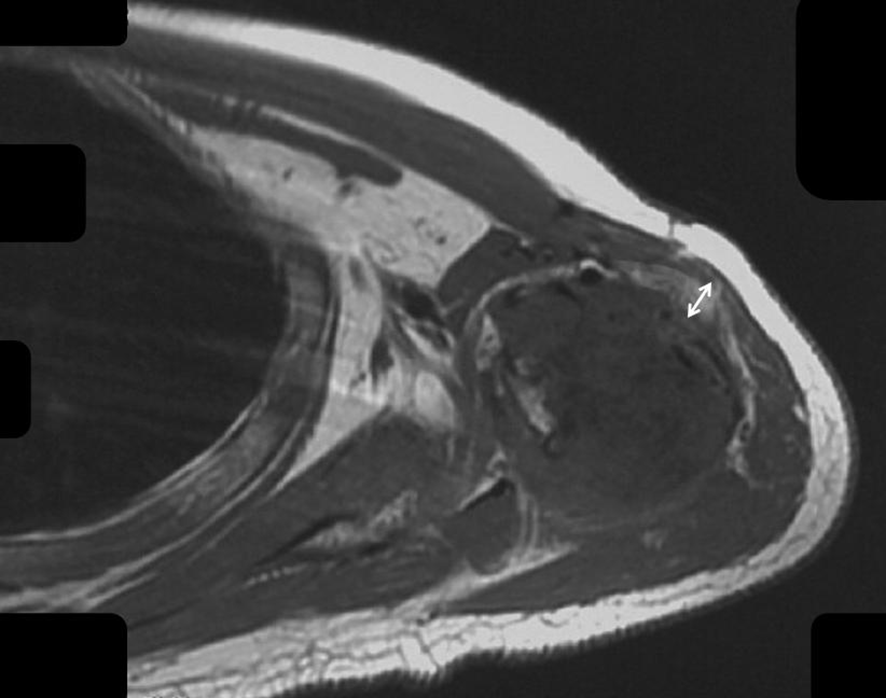

Figure 4

The fat layer around the humerus after chemotherapy is shown.

3.3 Presence of fat layer after chemotherapy

Fat tissue has short T1 times and shows bright signal intensity. The maximum diameter of the fat layer on transverse T1-weighted sequences was measured as its width. The average width of the fat layer emerging after neoadjuvant chemotherapy was 0.39 cm (range: 0.06 to 0.64 cm) (Figures 2–4). The best threshold values for the fat layer were confirmed using ROC curves (Figure 5). The area under the curve (AUC) was between 0.5 and 1.0. The AUC for the fat layer predicting necrosis was 0.759 (CI: 54.4%–97.5%). Furthermore, at a threshold value of 0.32 cm, the sensitivity and specificity for predicting tumor necrosis were 0.882 and 0.455, respectively. Using logistic regression analysis, the significance of the fat layer as a histological indicator of necrosis was 0.03. Moreover, an increase in fat layer width was associated with a favorable prognosis (p = 0.011; OR = 0.000; CI: 0.000–0.117).

MRI is specific and sensitive to fat tissue. Areas with high T1 signal intensity and low signal intensity based on fat suppression correspond to areas of fat tissue. A fat layer is commonly detected around the tumor after chemotherapy. However, studies on this topic have several limitations. We assumed a feature of the fat layer to predict prognosis. The extent of the fat layer was examined to determine its association with survival. The results illustrated that different fat diameters in T1 cross sections were independent predictors of EF survival. Indeed, increases in the width of the layer predicted higher survival rates. In our study, the logistic regression analysis indicated that the fat layer was a protective factor. The presence of a fat layer after chemotherapy limits the lesion and provides a safe excision edge in the soft tissue. Separating the main artery and nerve beyond the fat layer did not increase the risk of tumor recurrence. We also compared the width of the fat layer with necrosis and determined the relationship between the fat layer and chemotherapy response. Furthermore, we observed a difference in the chemotherapy response based on the extent of the fat layer in the early phase, which was in accordance with our hypothesis. Based on this characteristic, adjusting the chemotherapy regimen over time could improve survival and reduce the risk of resistance. Seeking an optimal predictor of chemotherapy response based on the tissue components, such as the fat layer, rather than tumor volume is crucial. The signal intensity evaluated on the MRI plane tended to be more effective than those evaluated based on volume-based tumor necrosis (22). The dynamic monitoring of the tumor’s response to drugs can be implemented based on MRI. If patients with poor response are identified early, the chemotherapy regimen or dose can be changed to improve outcomes. Moreover, if the tumor remains unresponsive to drugs, surgery can be prioritized to reduce the tumor burden.